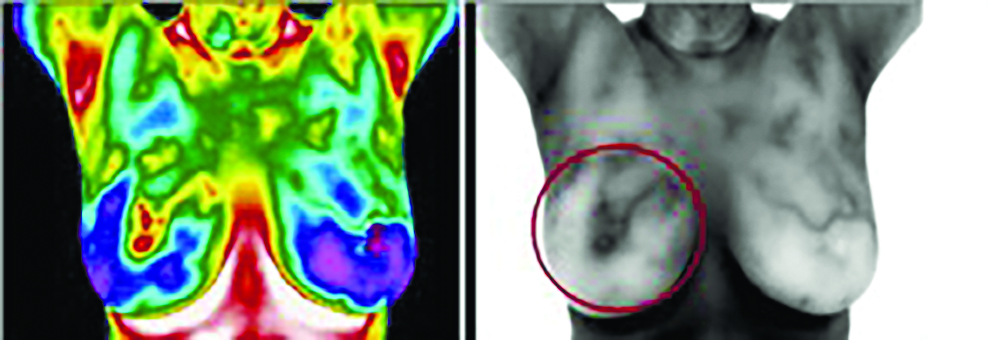

Заболевание молочной железы может быть выявлено путем поиска областей избыточной или повышенной температуры, которые могут указывать на области ангиогенеза или увеличения кровеносных сосудов, снабжаемых растущей опухолью.

- заболевания молочной железы (рак, фиброзно-кистозные образования, избыточный уровень эстрогена);

Термография используется для выявления рака молочной железы в Соединенных Штатах с 1956 года. Она была одобрена FDA в 1982 году. В рецензируемых журналах опубликовано более 800 исследований, посвященных термографии только одной молочной железы.

Большинство этих статей показывают успешность применения термографии молочной железы более 90% случаев. Так, исследование 2008 года в Нью-Йоркской пресвитерианской больнице в Корнеле, опубликованное в Americal Journal of Surgery, показало точность обнаружения на 97%.

Примеры диагностики